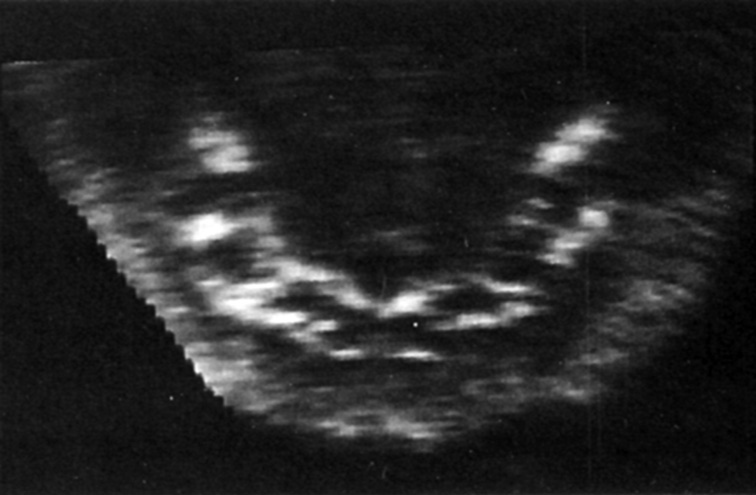

На полученных сонограммах у 15 беременных визуализировались все 20 зубных зачатков. Лицо плода помещалось на экран таким образом, чтобы можно было вывести профиль, а сдвиг и вращение изображения давали возможность осмотра верхней и нижней челюсти (рис. 8, 9). У трех беременных визуализация была затруднена. С использованием плоскостей сканирования, оптимизированных для исследования конкретного органа, осуществлялась визуализация нижней челюсти целиком, включая сочленение с верхней челюстью.

Рис. 8. Лицо плода / Fig. 8. Fetal face

Рис. 9. Зубные зачатки / Fig. 9. Dental rudiments